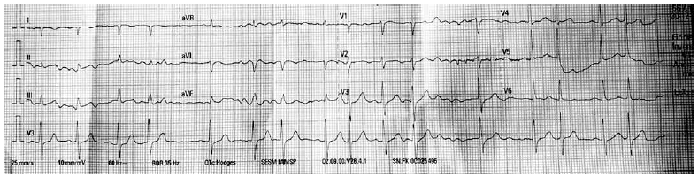

Durante o exame físico, foi observado que o ritmo cardíaco encontrava-se irregular. Foi realizado um eletrocardiograma, mostrado a seguir:

Foi feito o cálculo do intervalo QT corrigido pela fórmula de Bazett, 405 milissegundos. Assinale a alternativa correta a respeito do uso dos medicamentos que o paciente faz uso.

MANA, 85 anos, procura auxílio médico com história de sentir-se desanimada com fraqueza de membros inferiores. Vinha em uso de levotiroxina 50 mcg em jejum, omeprazol 20 mg em jejum, metoprolol 25 mg pela manhã, donepezila 5 mg/d, venlafaxina 150 mg/d e atorvastatina 20 mg/d. Durante exame físico, foi observada bradicardia, FC: 35 bpm. Foi realizado um eletrocardiograma, mostrado a seguir.